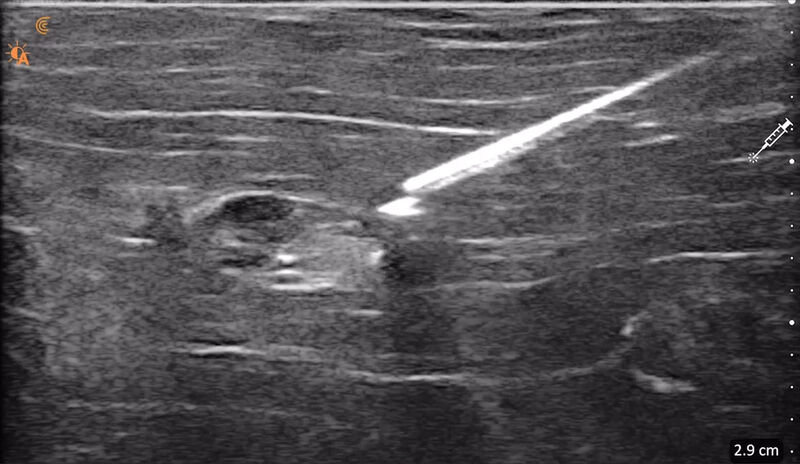

Visualize em cores e em tempo real a diferenciação entre as estruturas anatômicas. Tenha medidas automáticas e diversos recursos de otimização de imagem como o aprimoramento na visualização da agulha.